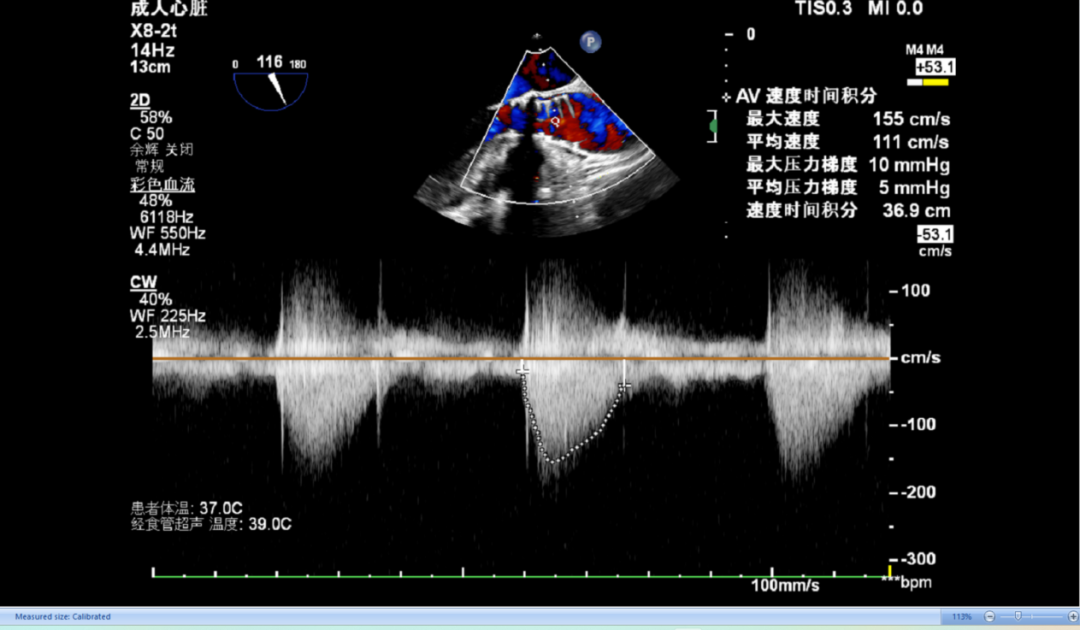

袁义强教授 河南省胸科医院(点击查看专家详细简历) 拥抱创新技术,推动心血管诊疗革新:作为医院管理者,我们团队始终把患者需求放在首位。干瓣作为TAVR的全新一代产品,其抗钙化性能预期为临床带来更卓越的耐久性,进一步延缓及降低二次手术的发生,每一个殷切期待眼神的患者身上,我们始终警醒,尽全力减少患者反复就医的痛苦,更从长远大幅节约医疗开支,让普通家庭看得起病、看好病。这不仅提升了诊疗效果,更践行了医疗惠民的初心,也多层面地减少医疗资源重复投入,为构建更经济高效的医疗体系注入动力,切实守护群众健康福祉。 孙玉梅教授 河南省胸科医院(点击查看专家详细简历) 念兹在兹,护佑患者每一刻:从医多年,我始终记得患者躺在病床上眼里饱含对健康渴求的殷切眼神,这是对医者的全心信赖——是把生命全然托付的信任,这份沉甸甸的情意,怎能辜负?选择什么手术策略,选择什么产品,医者需要给到专业意见的同时也需要听取患者的内心需求,既要保证当下手术的顺利成功,术后的快速恢复,更要为患者的长远生活兜底。Prostyle A 在这例重度钙化患者身上,既实现了术中安全植入、术后即刻改善,长久的抗钙化性能预期可以护航患者长期的生活。这份 “即刻与长久” 的平衡,正是我们一切从患者出发的初心写照,唯愿每一个细节里,都藏着让患者踏实的温度。 患者病史 主诉:间断胸闷、气促3年,加重两天。 既往史:平素健康状况良好。16 年前出现言语不清,就诊于当地医院,诊断为“脑梗死”给予药物治疗后症状好转。 术前 CT:Type1型(R-N)二叶瓣,右无交界存在钙化脊、粘连融合,极重度钙化,钙化集中在右无交界及三窦瓣叶边缘。 瓣环径27.1mm,LVOT28.9mm,瓣上3mm、6mm、9mm、12mm限制逐渐加重,从27mm逐渐缩窄至21mm。VTC空间较小,有一定冠脉风险。外周入路散在钙化、集中在双侧髂动脉与右股穿刺点后壁、双侧入路无明显迂曲,右股动脉内径可、低分叉。 手术策略 推荐右侧股动脉为主入路,瓣环27.1mm,Type1型(R-N)二叶瓣,右无交界存在钙化脊、粘连融合,极重度钙化,建议使用20mm球囊预扩,预装可回收AV23主动脉瓣膜,初始定位推荐真实瓣环上5mm超高位释放,释放时卸张力使瓣膜自然下滑至约瓣上1mm,利用瓣上限制固定瓣膜,提高封堵区封堵瓣上交界处,释放至工作位观察瓣膜情况决定是否回收。 手术过程 左右冠置入导丝进行冠脉保护 20号球囊预扩无明显腰征微量返流 初始定位 80%工作位观察 20号球囊后扩无明显腰征微量返流 术后造影:瓣膜形态好,有少量瓣周漏,冠脉造影无堵塞 术后超声:瓣膜形态好,有少量瓣周漏,平均跨瓣压差5mmHg Prostyle A®预装干瓣——“稳定支撑”助力临床最优化解决方案: 1. 平衡的径向支撑力:Prostyle A®综合设计带来平衡的径向支撑力,释放张力小,稳定贴靠,轻松应对高钙化病变; 2. Micro-EX™专利抗钙化技术:金仕生物专利抗钙化技术运用纳米技术去除组织内的细胞碎片和磷脂,封闭游离醛基,从根本上阻断了瓣膜钙化的多项因素,显著提升了瓣膜的耐久性;同时,相比较传统戊二醛保存方式,干式存储最大限度的保留心包的亲水亲油平衡,还原组织天然曲柔性,进一步保障了瓣叶开合,保证长期耐久性; 3. Prostyle A®平衡收腰设计:该例患者存在冠脉风险,Prostyle A®环上瓣及平衡的收腰设计,术后冠脉造影无堵塞,保证了有效瓣口面积的同时,带来更优异的血流动力学。